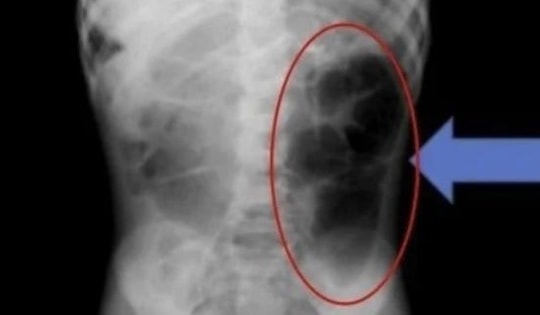

Người đàn ông 57 tuổi đau bụng thốc ngược lên, bác sĩ gắp ra thứ "đáng sợ" dài 5cm

Bệnh nhân nhập viện trong tình trạng đau hạ sườn phải lan xuống hố chậu phải, dễ nhầm lẫn với các bệnh lý như viêm đường mật, sỏi thận hay viêm ruột thừa. Bác sĩ phát hiện "bí mật" nằm trong bụng.